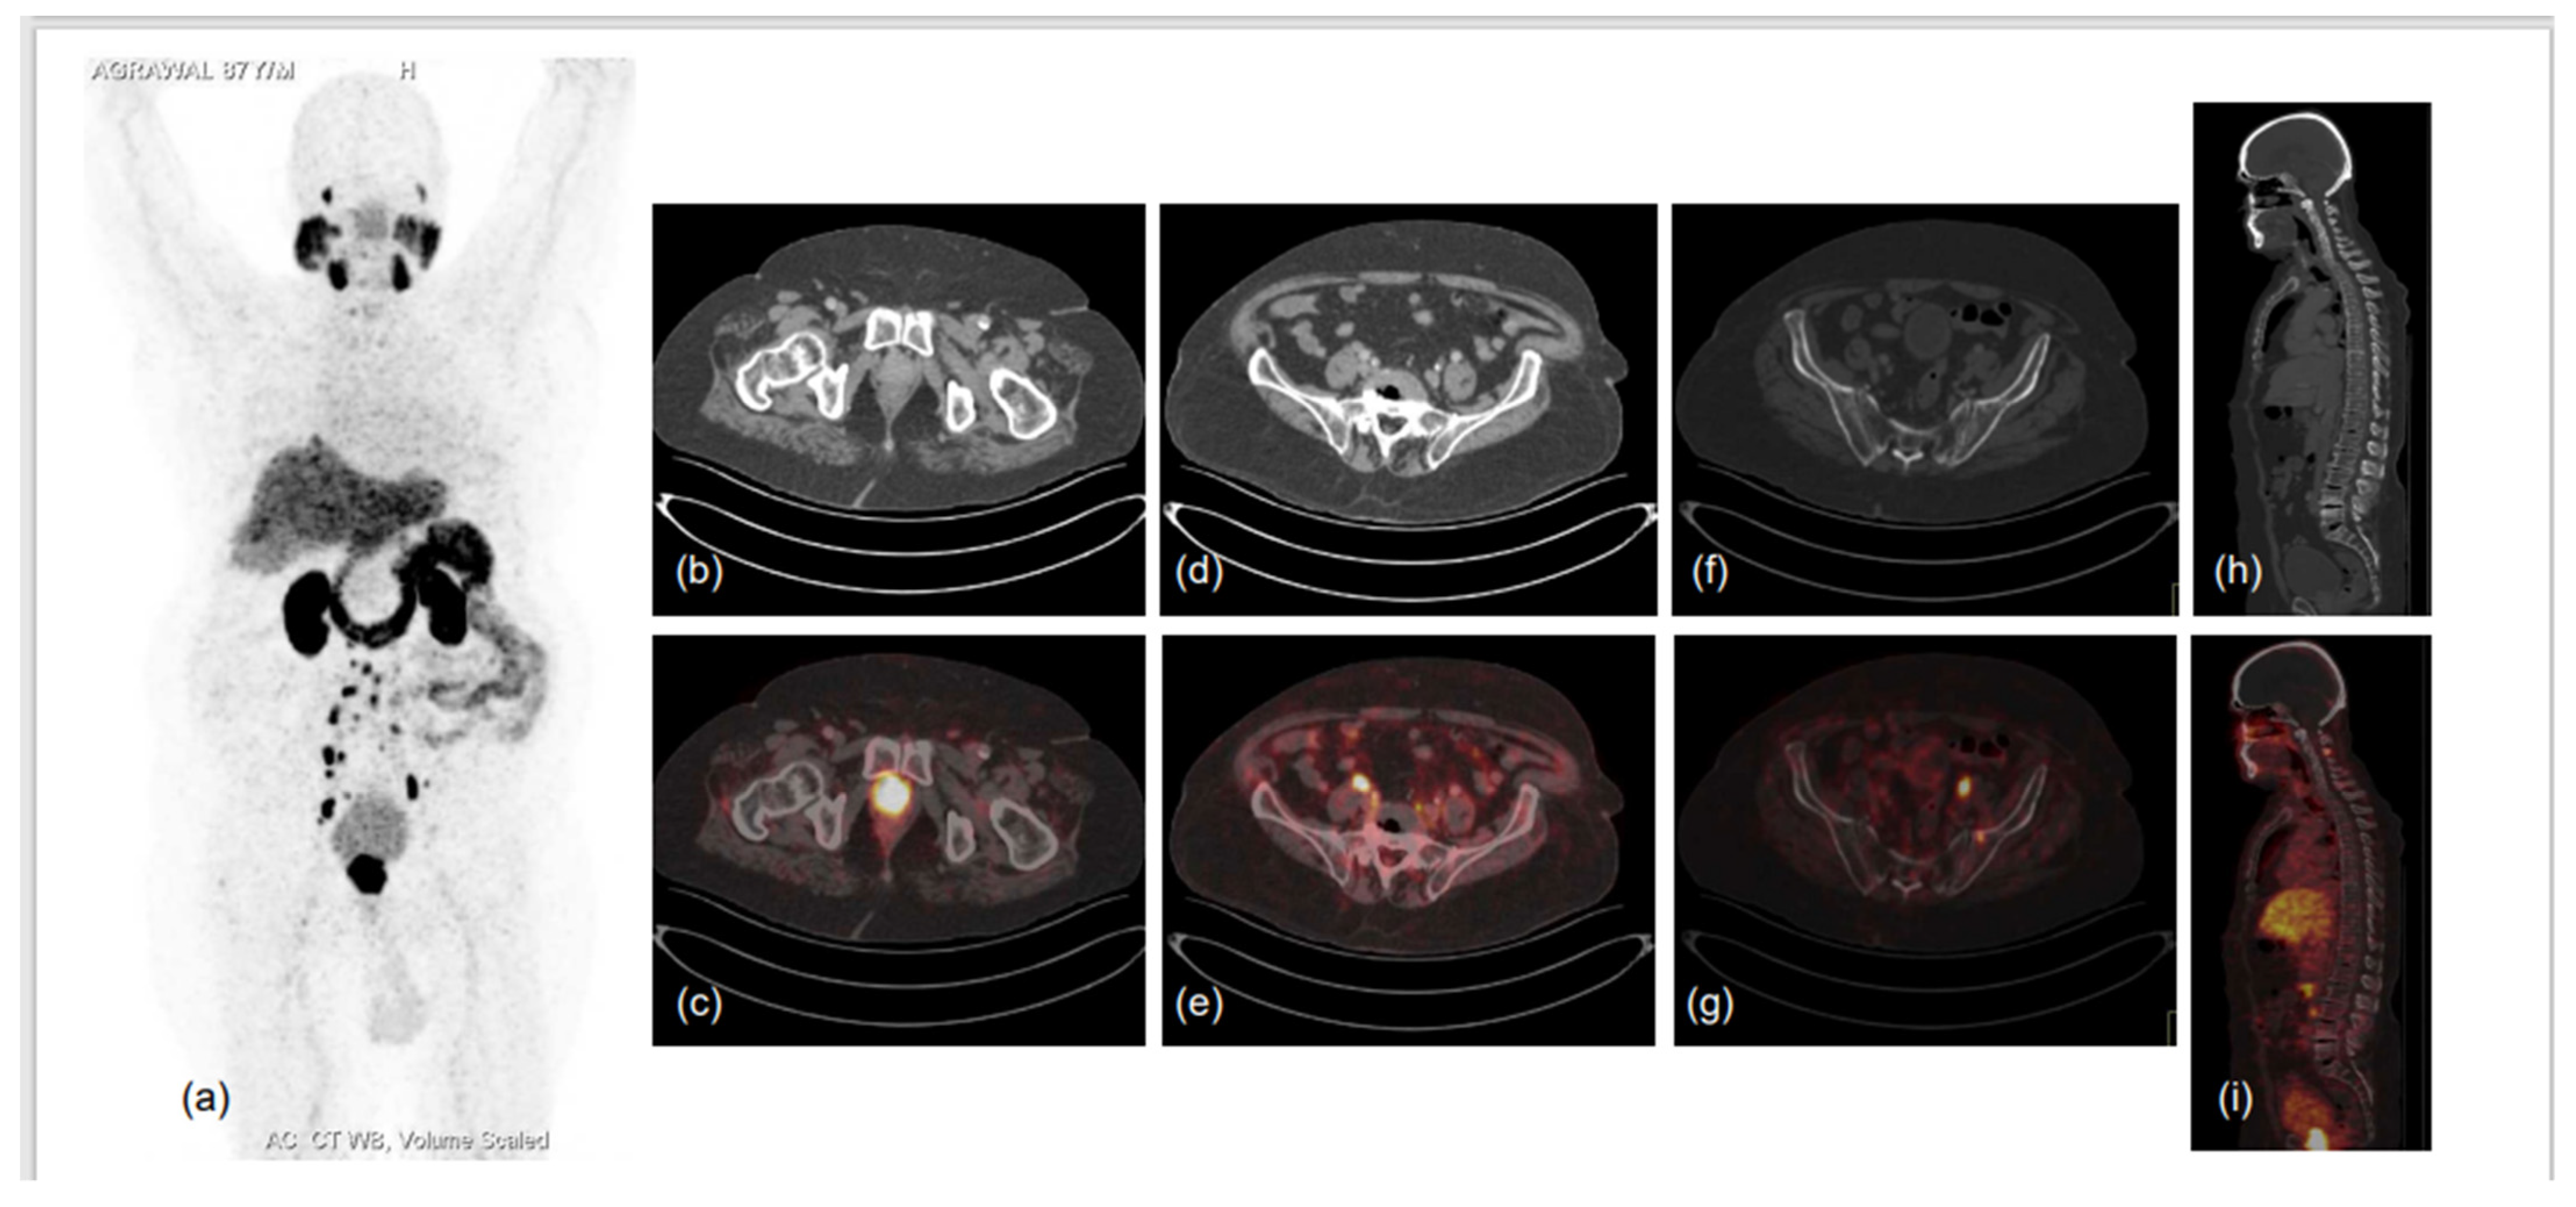

5. Biochemical Recurrence and Metastatic PCa